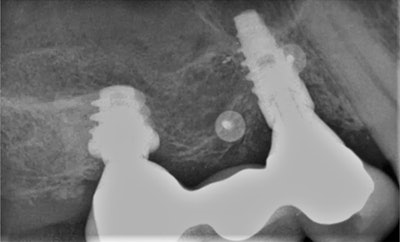

A 70-year-old patient presented to the dental practice for an emergency exam after experiencing pain around the peri-implant tissues of implant #5. On evaluation, sulcular pus and buccal edematous tissue were observed -- both associated with the implant in question. Following radiological studies of the affected area, implant #5 exhibited coronal bone loss and classic “cupping,” consistent with signs of occlusal overload. The patient received a diagnosis of peri-implant disease secondary to occlusal overload.

Because this was a complex case, an extensive treatment plan was developed, and advanced laser technology was used to maximize efficiency, effectiveness, and safety. Treatment consisted of debridement and disinfection with the Solea dental laser (Convergent Dental), a 9.3-µm CO2 laser, with guided bone regeneration.

The procedure began with careful ablation of the affected area, which included hard and soft tissues, for several minutes intermittently. The implant surface of #5 was lightly brush-stroked with the laser beam and then the bony defect was forcefully ablated. Laser application was continued until the site was clean and visually free of granulation tissue.

Because of the laser's design, fast and precise cutting was easy to achieve, as ablation only requires adding more (for hard tissue) or less (for soft tissue) pressure to its variable-speed foot pedal. Additionally, the 9.3-µm wavelength allowed for simple removal of the edematous tissue while maintaining the integrity of the tooth. Healthy bone remained, and the implant surface was not significantly altered. The water mist permitted thorough cleaning of the site visually, which aided in predictability.